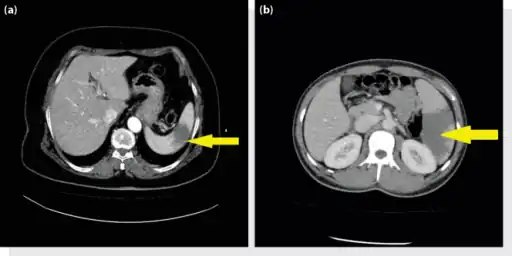

a, b) Splenic infarction.

Splenic infarct seen on CT

Although it can occur asymptomatically, the typical symptom is severe pain in the left upper quadrant of the abdomen, sometimes radiating to the left shoulder. Fever and chills develop in some cases.[3] It has to be differentiated from other causes of acute abdomen.

An abdominal CT scan is the most commonly used modality to confirm the diagnosis,[3] although abdominal ultrasound can also contribute.[16][17][18]